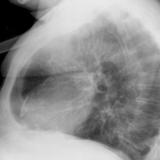

Case 1 Lat

Date: 03/17/2004

Views: 2983